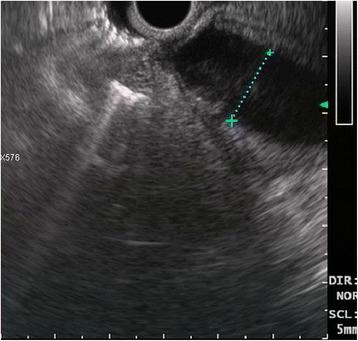

A 69-year-old woman was hospitalized in May 2016 for epigastric pain and weight loss. Her past medical history revealed an undefined main pancreatic duct dilation that was subsequently confirmed at CT scan (23 mm) and endoscopic ultrasound. There was no evidence of pancreatic masses, but the cephalic portion of the main pancreatic duct presented hypoechoic nodules. A diagnosis of the main-duct intraductal papillary mucinous neoplasm was made, and the patient underwent total pancreatectomy. Pathological examination showed a collision tumor constituted by a ductal adenocarcinoma involving the whole pancreas and a neuroendocrine tumor located in the duodenal peripancreatic wall and the head of the pancreas. There was one peripancreatic lymph node metastasis from the ductal adenocarcinoma and eight node metastases from the neuroendocrine tumor. These findings suggested a diagnosis of collision of neuroendocrine and ductal adenocarcinomas of the pancreas. The postoperative course was uneventful.

一名69岁女性于2016年5月因上腹部疼痛和体重减轻入院。她的既往病史显示有未明确的主胰管扩张,随后CT扫描(23毫米)和内镜超声证实了这一情况。没有胰腺肿块的证据,但主胰管头部出现低回声结节。诊断为主胰管内乳头状黏液性肿瘤,患者接受了全胰切除术。病理检查显示为碰撞瘤,由累及整个胰腺的导管腺癌和位于十二指肠胰周壁及胰头的神经内分泌肿瘤组成。导管腺癌有1个胰周淋巴结转移,神经内分泌肿瘤有8个淋巴结转移。这些发现提示胰腺神经内分泌癌与导管腺癌碰撞的诊断。术后过程顺利。